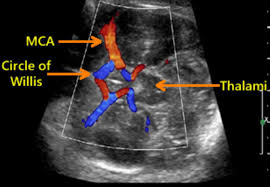

- Advanced Doppler (e.g. MCA) where clinically indicated.